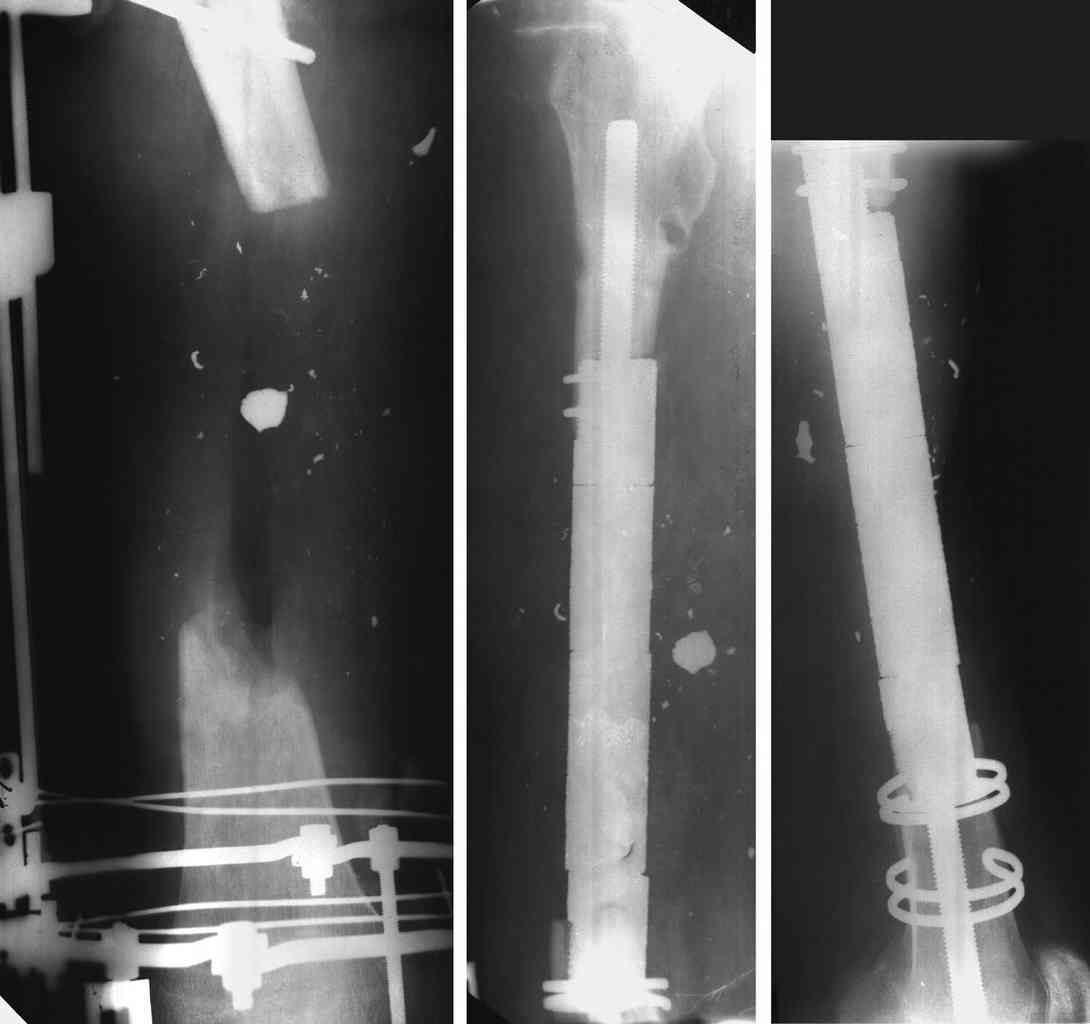

3 Diaphyseal endoprosthesis - see photo (dangerous in soft tissue loss and infection)

Similar case.

They do well with bone transport.

I do an acute or accelerated shortening to reduce the gap as much as proximal, and distract proximally to restore length.

In this particular case, notice the change of fixator - orthofix type of unilateral fixator worked well initially but did not allow me to compress beyond a point, which is when I changed to an ilizarov for further compression at the gap/nonunion site.